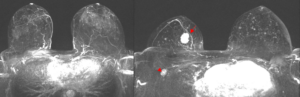

Magnetresonanz-Mammographie

Das bundesweite Mammographie-Screening richtet sich an Frauen zwischen 50 und 70 Jahren und ermöglicht die Entdeckung früher Veränderungen – oft noch bevor Beschwerden auftreten. Ergänzend kommt heute die Tomosynthese zum Einsatz, die durch Schichtaufnahmen die Bildqualität verbessert.

Dennoch reicht die Mammographie allein nicht immer aus. Gerade bei jüngeren Frauen mit dichtem Brustgewebe können kleine oder diffuse Veränderungen schwer erkennbar sein.

Daher bieten wir zusätzlich die MRT-Mammographie als besonders sensibles Verfahren an. Sie kommt ohne Strahlenbelastung und ohne schmerzhafte Kompression aus. Während der etwa 20–25-minütigen Untersuchung in Bauchlage wird nach Gabe eines gut verträglichen Kontrastmittels die Durchblutung der Brust dreidimensional dargestellt. So können auch kleinste oder aggressivere Tumorformen zuverlässig erkannt werden.

Neuere Studien zeigen, dass die Magnetresonanz-Mammographie deutlich mehr tumoröse Veränderungen als die konventionelle Mammographie erfasst und die Prognose der Patientinnen signifikant verbessert(3),(4). Die außerordentlich hohe Empfindlichkeit („Sensitivität“) der Methode führt auch dazu, dass die Wahrscheinlichkeit eines innerhalb des üblichen Zweijahres-Zeitraums zwischen den Screening-Mammografien erstmals nachweisbaren Tumors (sog. „Intervallkarzinome“) gegen Null tendiert(5). Im Umkehrschluss gilt: Zeigt die Magnetresonanz-Mammographie keine Auffälligkeiten, kann weitgehend risikolos auf eine Biopsie verzichtet werden.

Auch bei Frauen, bei denen bereits Brustkrebs festgestellt wurde, hilft die Magnetresonanz-Mammographie weiter, da sie das Ausmaß der Erkrankung genauer erkennen lässt und einen eventuellen Befall auch der anderen Brust zeigt, der in immerhin 3-5% der Fälle vorliegt, so dass dann eine entsprechende Optimierung der Therapie möglich wird(6),(7). Insbesondere Frauen vor den Wechseljahren mit häufig noch dichtem Brustdrüsengewebe profitieren von einer präoperativen Magnetresonanz-Mammographie(8).